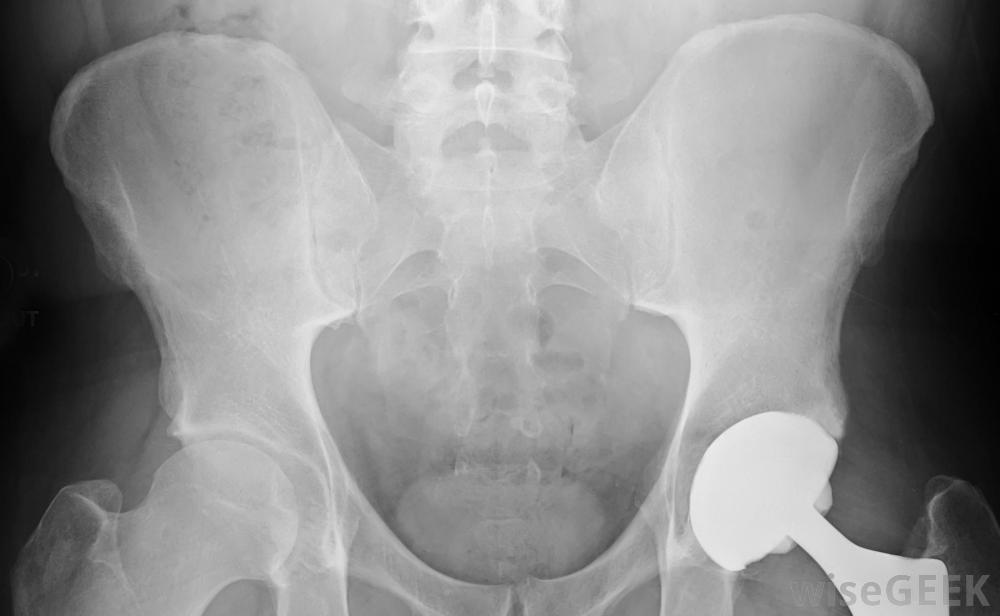

植入假體的手術會導致并發癥

有并發癥的風險和價格。許多保險公司會為這些設備的安裝和購買提供保險,但是那些沒有保險的人可能會比較困難。一些醫生和制造商可能會考慮付款計劃,但情況并非總是如此。

假肢也有潛在的健康問題與假肢有關。許多假肢會導致皮膚問題一些患者在使用這種新的治療設備時,需要花費大量的時間和精力,因為在許多情況下,有必要重新培訓和重新學習如何使用某些肌肉群。